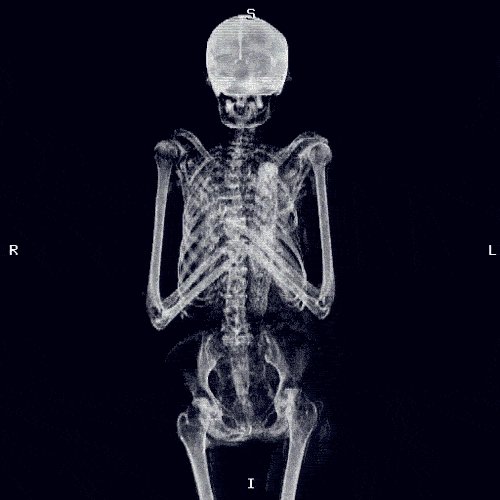

من مكونات المناعة في أجسامنا :

الخلايا المناعية والخلايا الطبيعية القاتلة الي تفرز انزيمات ومواد قاتلة واللوزتين تعتبر حارس حيوي بالإضافة للكبد(الطحال) الي تنقي الدم من السموم والجراثيم وبعض المواد الكيميائية النافعة والمسالك البولية .

فيه ثلاث حواجز رئيسية للمناعة في جسمنا:

١- البشرة: جلدنا فيه باكتيريا نافعة وتعتبر صديقة لنا وهي خط دفاع أولي يساعدنا في حماية جسمنا من الغزو الخارجي وفيه دهون وأحماض غير الباكتيريا أسمها (فلورا) تحسبون بس كذا؟ لا

٣- يُعتبر الإلتهاب طريقة حماية للجسم وتعد كريات الدم البيضاء الخلايا الأساسية في جهاز المناعة لأنها تصنع الحموضة اللازمة لإذابة المايكروبات والعوامل الممرضة والسم للقضاء عليها وإطلاق بعض الانزيمات الي تذيب المايكروبات.